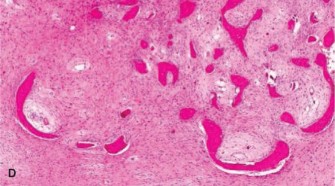

For Atypical Cartilaginous Tumors, a cortical window is created over the lesion. The window should be oval or rectangular with rounded corners to minimize stress risers. The window must be large enough to allow complete visualization of the tumor cavity.

Intralesional curettage is performed systematically. Hand curettes are used to remove the gross macroscopic tumor, which typically appears as glistening, bluish-white, avascular lobules of cartilage. Following gross removal, a high-speed mechanical burr is utilized to extend the curettage 1 to 2 millimeters into normal-appearing cancellous and cortical bone. This mechanical adjuvant is critical for removing microscopic tumor extensions within the trabecular bone.

Image

Chemical or physical adjuvants are subsequently applied to the cavity to induce necrosis of any remaining microscopic disease. Phenol (followed by alcohol neutralization), hydrogen peroxide, or liquid nitrogen (cryotherapy) are commonly employed. When using cryotherapy, careful protection of the surrounding soft tissues and neurovascular structures is imperative to prevent iatrogenic thermal injury. Multiple freeze-thaw cycles provide the maximum tumoricidal effect.